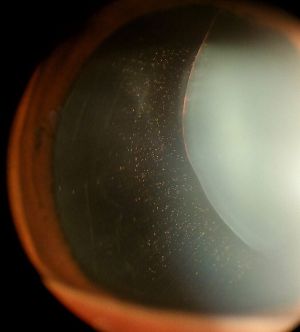

- Ectopia lentis

- Ocular Lens dislocation, retinal detachment

- Initial evaluation often occurs in the outpatient setting and involves a thorough physical exam for identification of classically associated features, review of family medical history, slit lamp dilated pupil eye exam (to evaluate for ectopia lentis), and echocardiogram.

- Aortic Root Dilatation Z Score > 2 and Ectopia Lentis

- Ectopia Lentis and Family History of MFS